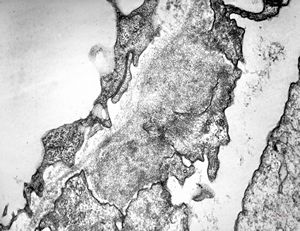

M,22y. | type II membranoproliferative glomerulonephritis